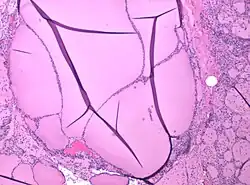

Colloid nodule

Histopathology of a colloid nodule of the thyroid, showing dilated thyroid follicles. There is some reactive fibrosis (at right) but no consistent capsule.

Colloid nodules are distinguished by an apparently gelatinous mass of colloid both surrounding and contained within follicular cells. Colloid nodules are not surrounded by a fibrous capsule of compressed tissue. However, they are surrounded by flattened epithelial cells.[8] Both the number of cells and the type of colloid may vary considerably.[7]